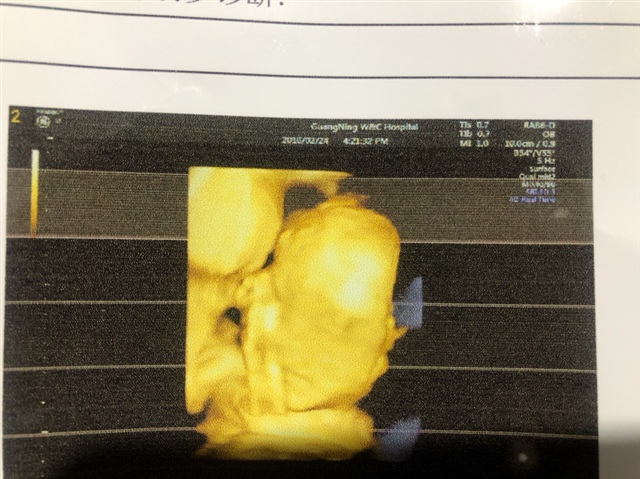

产前检查 B超